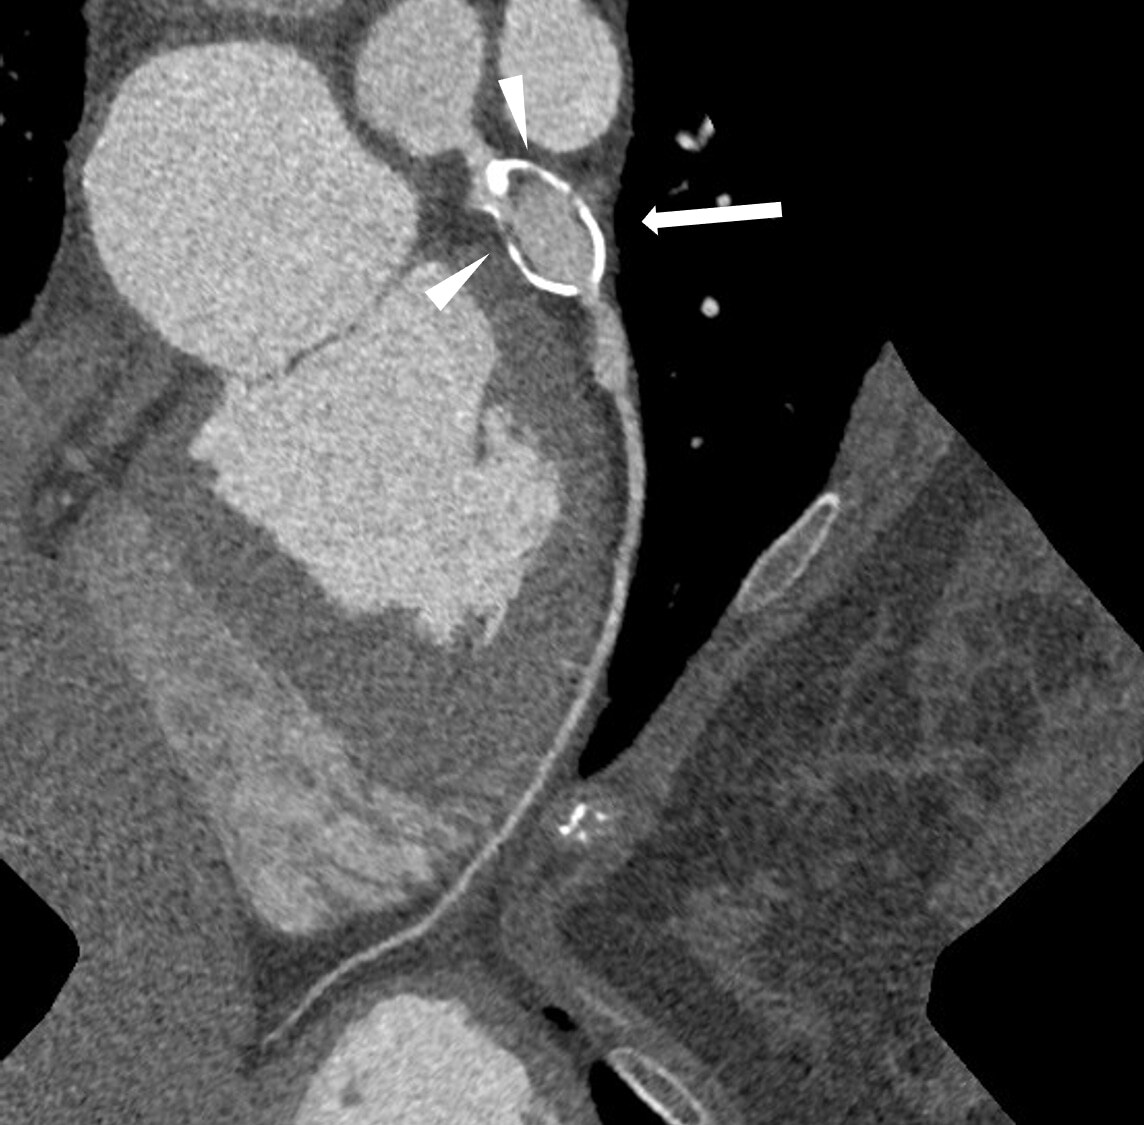

図2.Angiographic View

#6に石灰化を伴った16㎜大の巨大動脈瘤(➡)、#7に石灰化を伴わない動脈瘤(➤)を認める。